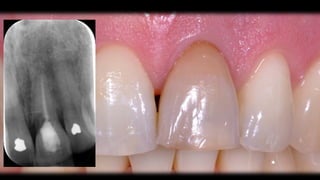

21 internal root resorption, discoloured

slight crowding 21,11

buccally positioned 11,21

buccal recession 11 and 21